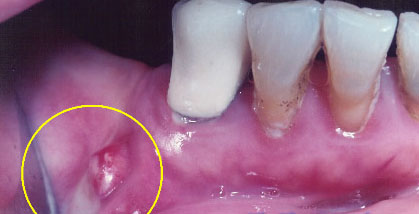

Hình: áp xe ở răng cửa hàm trên. Trường hợp này phải điều trị khẩn bằng cách rạch abcess để thoát mủ.